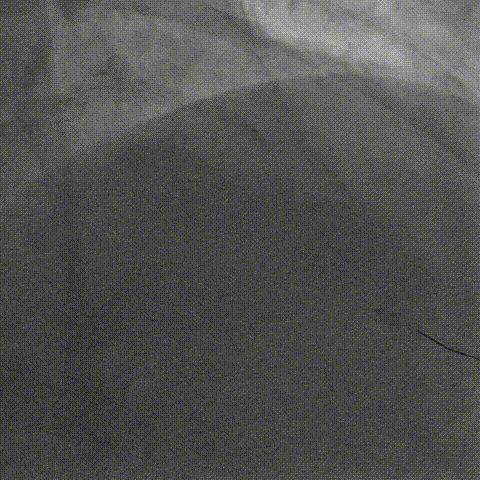

左冠造影

右冠造影